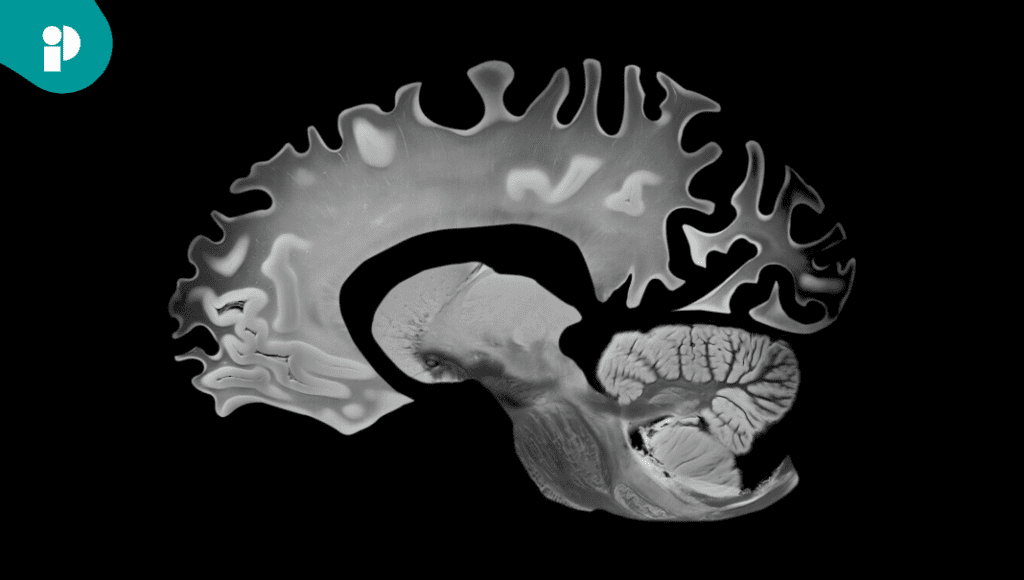

Un nuevo análisis del ensayo clínico TRAILBLAZER-ALZ 2 reveló que los pacientes con enfermedad de Alzheimer (EA) sintomática temprana que alcanzaron niveles más bajos de amiloide después del tratamiento con donanemab experimentaron un deterioro cognitivo y funcional más lento y mejoras en varios biomarcadores asociados a la enfermedad.

Los resultados muestran que una mayor reducción del amiloide cerebral se asocia estrechamente con una menor progresión de la enfermedad y con descensos en los niveles de tau fosforilada y proteína fibrilar glial (GFAP), dos marcadores clave del daño neuronal y la inflamación cerebral.